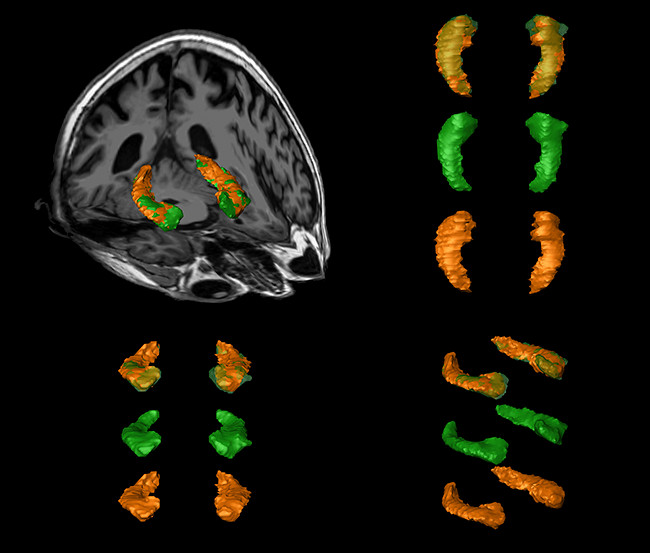

AOM de los hipocampos de un sujeto realizado por los dos operadores en rojo (A) y amarillo (B). Se observan las reconstrucciones volumétricas de las formaciones hipocampales, superpuestas a una secuencia volumétrica ponderada en T1 en posición oblicua (imagen superior) y en posiciones sagital, axial y coronal (imágenes inferiores).

AOM de los hipocampos de un sujeto vs análisis objetivo automático (AOA). Se observan las reconstrucciones volumétricas de las segmentaciones manuales (en verde), automáticas (en naranja) y sus fusiones (en verde-naranja) de las formaciones hipocampales. En la esquina superior-izquierda, en una vista oblicua superpuestas a una secuencia volumétrica ponderada en T1, en la esquina superior-derecha en una vista superior, en la esquina inferior-izquierda en una vista anterior y en la esquina inferior-derecha en una vista oblicua.